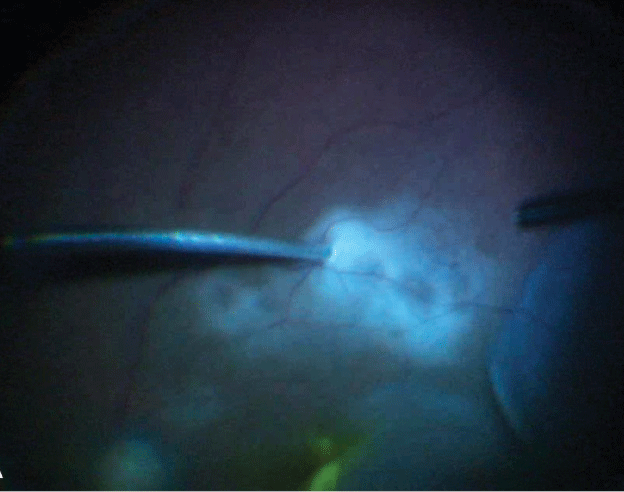

![]() |

| Figure 2. Retinal tissue is aspirated into the vitreous cutter tubing confirmed on visualization (black arrows). |

5. Aspirate tissue for biopsy. If a retinal biopsy is indicated, a 27-gauge cutter can be directly introduced into the retina or subretinal space (Figure 1) and the tissue aspirated using high vacuum (~600 mmHg) and low cut rate (~300 to 500 cpm). Once you visualize the specimen in the infusion line (Figure 2), withdraw the cutter and reflux the sample into the collection tube (Figure 3). Alternatively, a larger piece of retinal tissue may be harvested using scissors and carefully extracted through an enlarged sclerotomy. In such cases, the retinotomy is barricaded with endolaser. Intraocular tamponade is usually used.